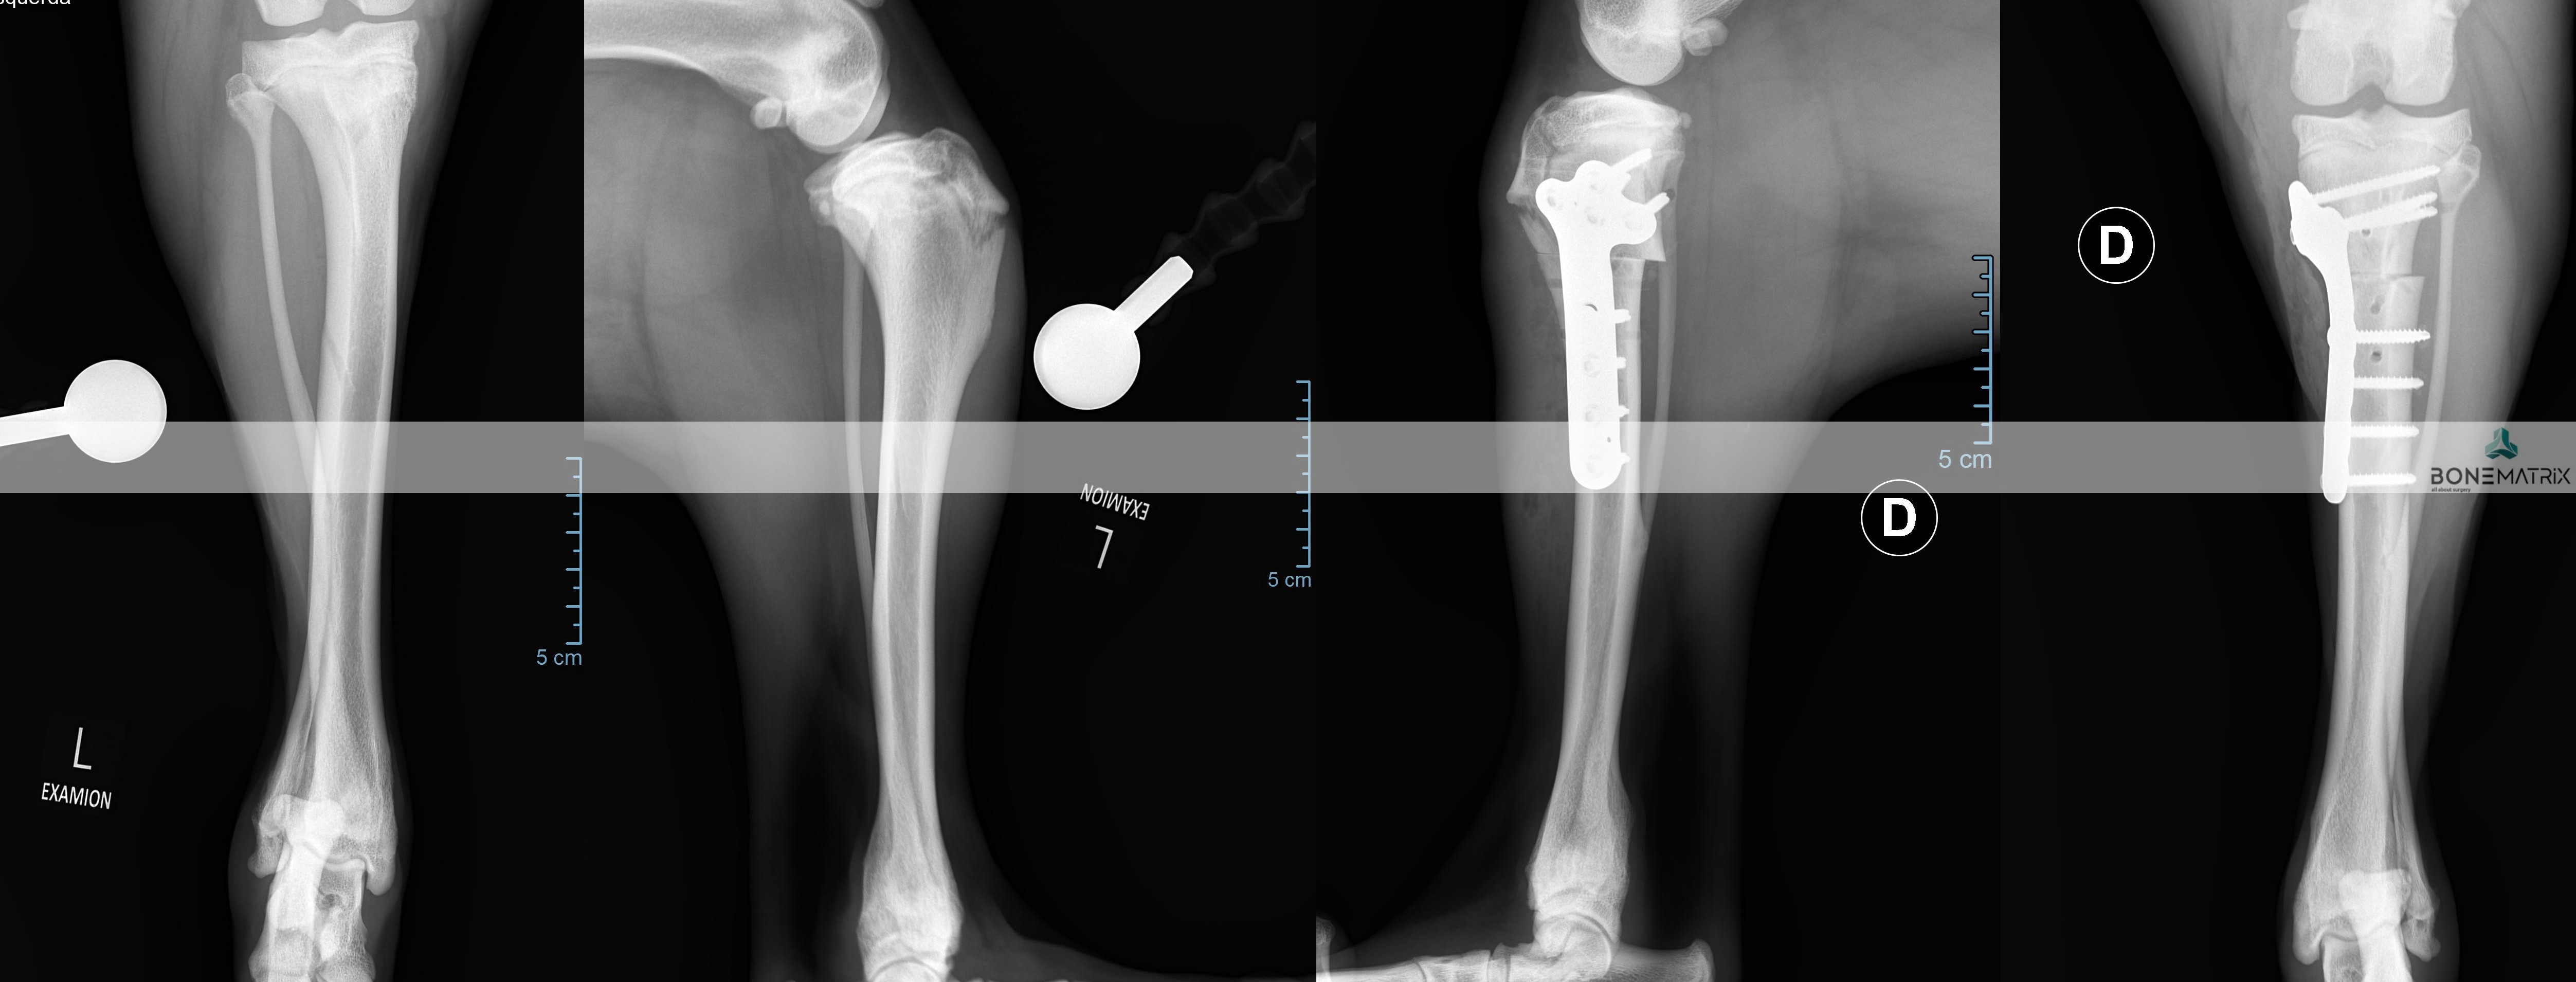

A TPLO é a técnica universalmente aceite na comunidade cientifica como sendo a opção terapêutica que garante melhores resultados no tratamento da rotura de ligamento cruzado cranial. Ainda assim, existem casos onde outras técnicas possam ser mais vantajosas pelo que o domínio de várias técnicas cirúrgicas representa uma vantagem determinante na seleção da melhor opção para tratar o seu animal.

A TPLO tem como objetivo alterar a forma como as cargas atravessam o joelho, para que se consiga um equilíbrio de forças que restaura a estabilidade articular. Desta forma não se tenta reparar o ligamento cruzado danificado, mas sim conseguir uma estabilidade dinâmica que torne desnecessária a existência de um ligamento cruzado íntegro.

Esta alteração acontece após um corte circular controlado no qual o fragmento criado é rodado e estabilizado na nova posição com recurso a implantes (placa e parafusos bloqueados).

Quais das vantagens da TPLO sobre outras técnicas cirúrgicas?

Em estudo comparativos entre a técnica de resolução de patologia de rotura do ligamento cruzado cranial foi provado existir uma maior aplicação de força sobre o membro intervencionado, uma maior satisfação do cliente e uma melhor função do membro, quando utilizada a técnica de TPLO.

Este estudo também demonstra que quando aplicada a técnica de TPLO a função do membro após um ano é indistinguível do grupo de controlo (onde o ligamento não tem lesão).

O desenvolvimento de osteoartrite também é um fator bastante relevante para avaliação do outcome destas técnicas, pois esta doença provoca o desenvolvimento de dor crónica articular que poderá ter um caracter limitante na qualidade de vida do animal. Estudos indicam que existe uma menor progressão de osteoartrite quando a TPLO é aplicada, em comparação com outras técnicas.

Qual a taxa de sucesso esperada?

Esta cirurgia tem uma taxa estudada de sucesso de 95% dos casos.

A execução precisa da técnica de TPLO influencia a eficiência do procedimento e o acometimento de complicações cirúrgicas.